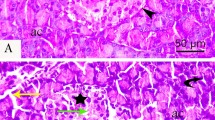

In vivo PCB126 exposure did not alter islet of Langerhans morphology and viability, but exacerbated free radical production

In vivo PCB126 exposure evoked significant increase in protein expression of AhR on islets of Langerhans (Fig. 3a), but had no effect on insulin secretion (Fig. S4A), islets morphology (Fig. S4B), viability (Fig. S4C), or cell cycle (Fig. S4D). Nevertheless, in vivo PCB126 exposure evoked a significant exacerbation of peroxynitrite generation on islets of Langerhans (Fig. 3b,c) while having no effect on superoxide anion production (Fig. 3d,e). Ex vivo incubation of islets of Langerhans with different concentrations of glucose showed that at physiological glucose levels (11.4 mM), the NO production was similar in islets collected from vehicle or PCB126 exposed rats; nevertheless, significant increases in NO levels in islets from rats exposed to PCB126 were detected when islets were cultured in high glucose medium (16.7 mM) (Fig. 3f).

Effects of in vivo PCB126 10 μg/kg exposure on free radical generation on islets of Langerhans.

(a) Bars graph and representative image of AhR expression on islets of Langerhans. Representative image and bars graph showing peroxynitrite (b,c) and superoxide anion production (d,e). Determination of NO production (f) in islets cultured at physiological (11.4 mM) or high glucose levels (16.7 mM). Data were analyzed by student’s t-test (a,c,e) or two-way ANOVA (f). *P < 0.05; ***P < 0.001 vs. vehicle group.